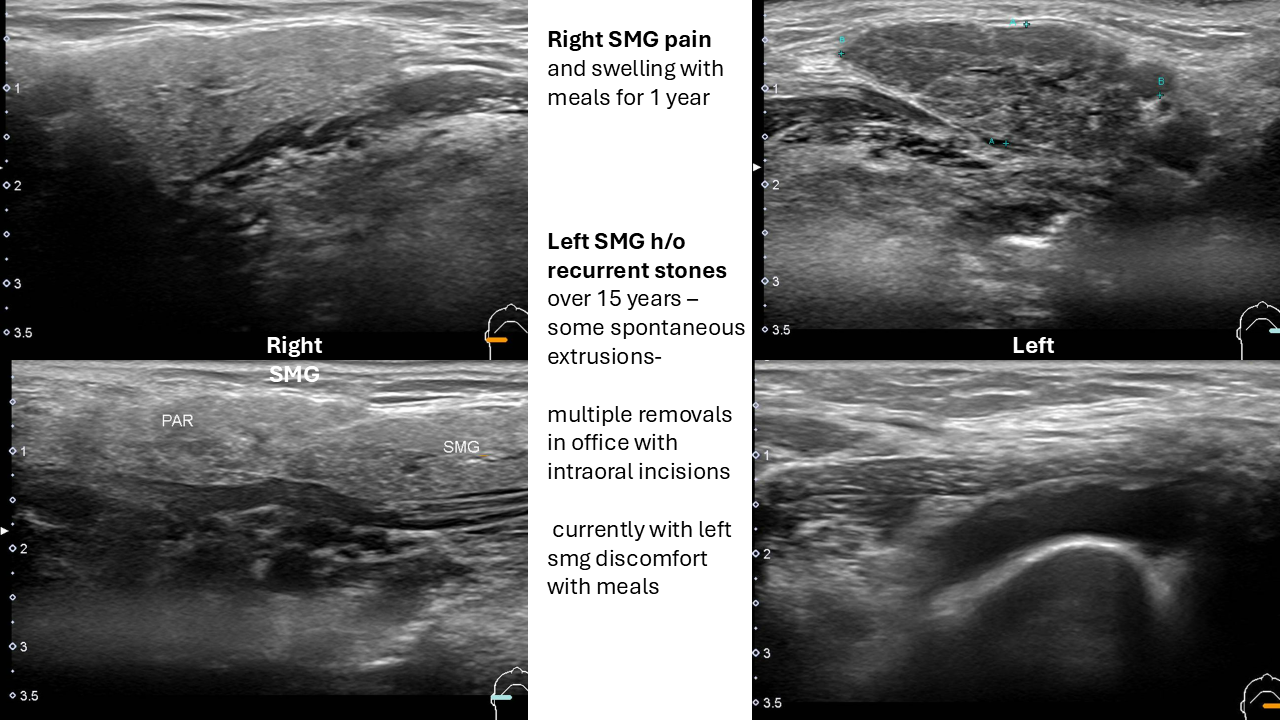

78 yo with

Right SMG pain and swelling with meals for 1 year

Left SMG h/o recurrent stones over 15 years –

- some spontaneous extrusions

- multiple removals in office with intraoral incisions

- currently with left smg discomfort with meals